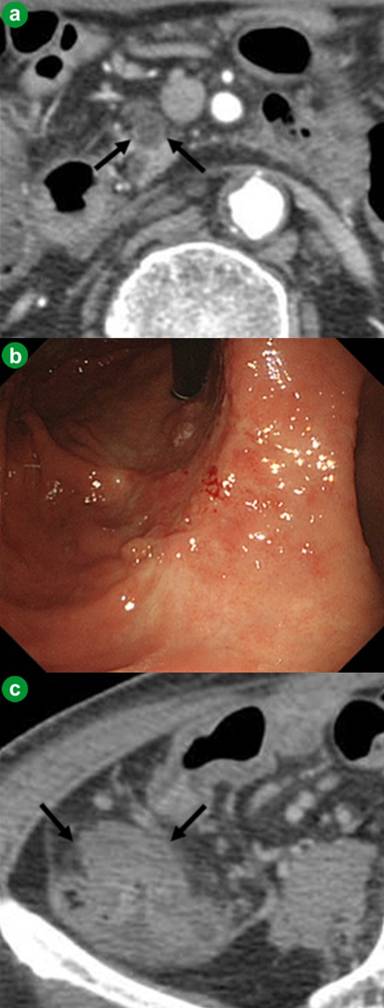

Because invasive surgery, including resection of the portal venous system, was required to remove all three tumors and the patient had risk factors for surgery, including older age and diabetes mellitus, we elected to treat him with chemotherapy. He was treated with cycles of 100 mg/day S-1 (TS-1, Taiho Pharmaceutical Co., Ltd., Tokyo, Japan) for 2 weeks, followed by a 1-week rest; the dose of S-1 had been reduced from 120 mg/day to 100 mg/day because of his older age. After 4 cycles of S-1 chemotherapy, the pancreatic head tumor decreased from 22 mm to 10 mm in diameter (Figure 3a), or 55% according to the Response Evaluation Criteria in Solid Tumors (RECIST) [11]. Upper gastrointestinal endoscopy and CT showed marked reductions in size of the gastric and cecal tumors, respectively (Figure 3bc). DUPAN-II was markedly reduced from 5,750 U/mL to 1,550 U/mL (Figure 4). The patient experienced no definite adverse effects of S-1, according to the Common Terminology Criteria for Adverse Events (CTCAE) version 4.0 [12].

Figure 3. Effects of S-1 chemotherapy on the three tumors. a. Enhanced computed tomography showing that the pancreatic head tumor had decreased from 22 mm to 10 mm in diameter (black arrows). b. Upper gastrointestinal endoscopy showing marked decrease in the size of the gastric tumor. c. Computed tomography showing markedly decrease in the size of the cecal tumor (black arrows). |